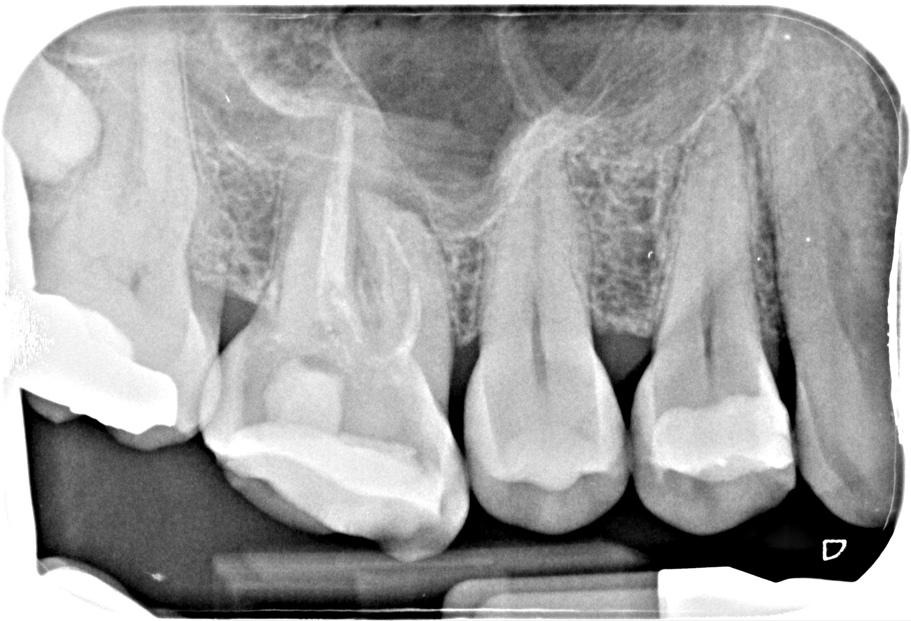

Pre-op IOPA

‘Sometimes it really does pay to keep an open mind.’ This was initially sent to me as a file retrieval case. I think when the referral letter indicates there is a broken file, its easy to become influenced by this and develop ‘tunnel vision’ in the way that you view it. A fresh pair of eyes is often beneficial. I asked Simon Barnwell (Simply endo mentor) for his opinion and he felt this did not look like a broken file in the mesial root. A CBCT scan was taken to help assess the restorability of this tooth and showed the following: